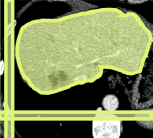

Consider a three-dimensional object within a volume. It is straightforward to produce a 3D bounding box of the object by finding its extreme points in the three coordinate axes. While this 3D bounding box will be tight in the 3D sense, its rectangular cross-sections will not, in general, remain tight with respect to the planar cross-sections of the volume. Fig. 1 illustrates such a case for the task of liver segmentation in a CT volume. In the Experiments section we show that the success of existing 2D weakly-supervised segmentation methods relies on the bounding boxes being tight and therefore the tightness of the individual 2D bounding boxes should be corrected before training and applying a segmentation CNN.

The global bounding box tightness prior mentioned above assumes that each of side of the box is sufficiently close to the target region. This means that for any region shape, each vertical or horizontal line inside the bounding box will cross at least one pixel belonging to the target region. This condition does not hold when the provided annotation comes as a 3D bounding box which is represented as a series of per-slice non-tight 2D bounding boxes. In this case, there will exist vertical or horizontal lines shown as stripes in Fig. 1 (d), that will lie outside of the actual object boundary. In the Experiments section we demonstrate the poor performance of the weakly-supervised approach from [5] when the user-provided bounding box is much wider than the true object of interest.